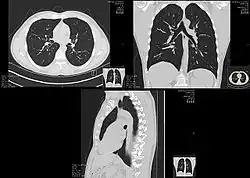

A CT scan can be used for detecting both acute and chronic changes in the lung parenchyma, the tissue of the lungs.[41] It is particularly helpful because normal two-dimensional X-rays do not show such defects. A variety of techniques are used, depending on the suspected abnormality. For evaluation of chronic interstitial processes such as emphysema, and fibrosis,[42] thin sections with high spatial frequency reconstructions are used; often scans are performed both on inspiration and expiration. This special technique is called high resolution CT that produces a sampling of the lung, and not continuous images.[43]

HRCT images of a normal thorax in axial, coronal and sagittal planes, respectively.